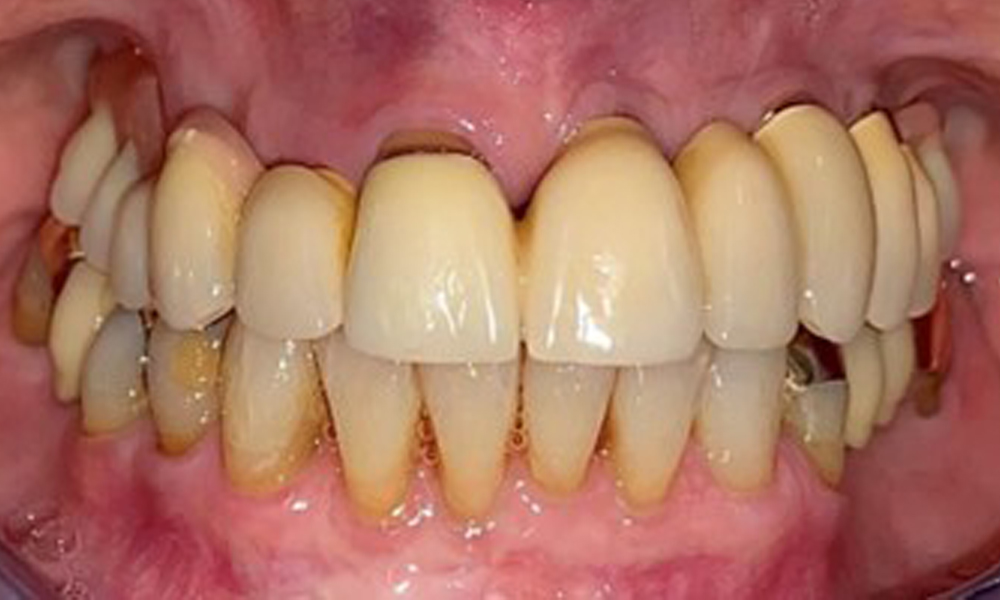

Frontal view with the maxillary denture in situ.

Fig. 1: Frontal view with the maxillary denture in situ.

The patient was fitted with a combined removable maxillary telescopic prosthesis more than 25 years ago (Fig. 1, Fig. 2, Fig. 3) and is very happy with her dentures. The patient has an adequate fixed denture for the mandible (Fig. 4).

The dental findings are as follows: Combined removable implant and tooth-supported telescopic prostheses on implants 15, 13, 21, 23, 24, 25 and tooth 11 (Fig. 1, Fig. 2, Fig. 3). The patient was fitted with a fixed mandibular denture. Adequate bridges were present over 37 to 34 and 45 to 47 (Fig. 4), the crown margins were intact and there were no active caries. A composite filling with a marginal gap was present on tooth 43. There was mandibular gingival recession, exposing 1 to 3 mm of root surface. This also applies to 11.